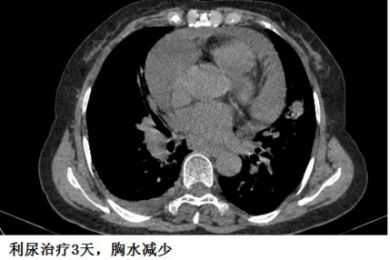

下面这个患者,纵膈淋巴结肿大、融合,心包积液,胸腔积液,一看就是晚期肺癌。后来,纤支镜也确实查到癌细胞。

这个胸水,不好抽,但也不难抽。癌性胸水,不抗癌治疗,不引流,一般不会自行吸收。我带同学去抽胸水,为了安全起见,我事先还是用B超探查了一下胸水,我瞬间就懵了:居然只有极少量的胸水。

复查CT,“癌性胸水”果然无缘无故减少了。

这个患者的胸水,应该是心包积液导致静脉回流受阻,体循环淤血引起的。利尿治疗后,胸水减少。